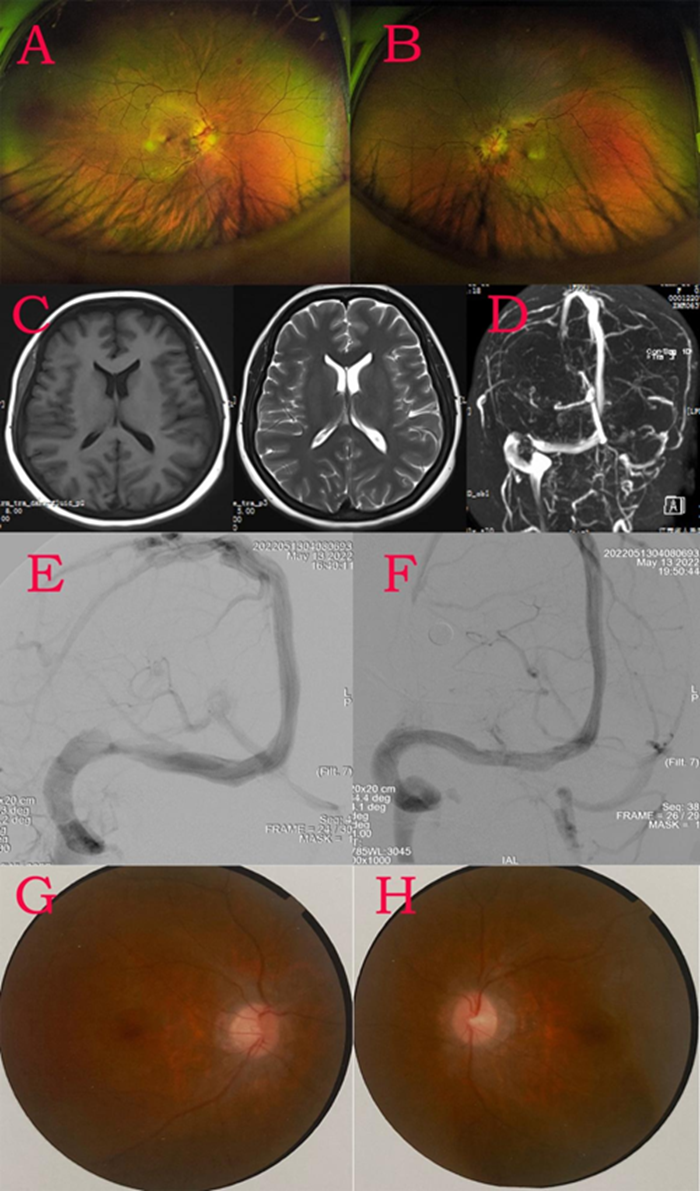

患者袁女士,头痛、头晕、恶心呕吐6天,为全头胀痛,伴有恶心呕吐,呕吐物为胃内容物,无咖啡色液体,既往2年还有高血压病,口服拜新同降压,近期自行停药。入院后给予降压及对症支持治疗,患者头痛、头晕仍未改善,5月10日开始出现视力下降,测试视力“指数”,眼底检查示双侧视乳头水肿,OCT提示双眼球动脉未见显影,静脉淤血(图A-B)。5月11日行头颅MRI未见明显异常,MRV提示左侧横窦发育不良,右侧横窦狭窄可能(图C-D)。腰穿示脑脊液压力>330mmH2O(爆表),脑脊液常规、生化、细胞学等均正常。5月13日视力持续下降,已经不能看到手机解锁密码,视力仅有光感。5月13日脑动脉造影提示左侧横窦未见明显显影,右侧横窦狭窄(图E),静脉窦测压提示狭窄远端压力为34mmHg,狭窄近端为13mmHg,远近端压差21mmHg,具有手术指证(一般>8mmHg或症状性>6mmHg)。

全麻下,医护人员为袁女士置入静脉窦支架后狭窄解除,复测支架远近段压力均为20mmHg(图F)。5月14日晨起后患者头痛、头晕缓解,并且已经可以正常使用手机。5月16日复查腰穿,脑脊液压力210mmH2O。6月11日门诊复查,OCT提示双眼底视乳头正常,动静脉比例正常(图G-H)。